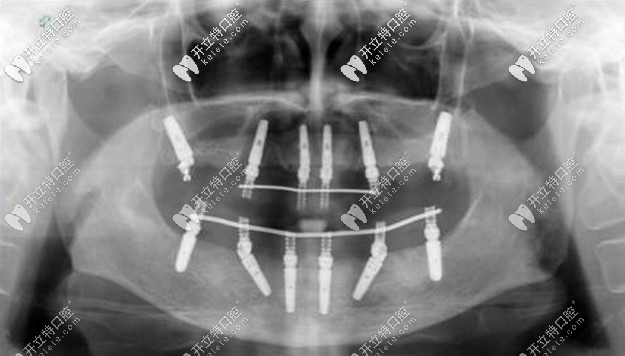

老人種牙All-on-4全口種植牙——價(jià)格在16萬-25萬之間,上下牙各四顆種植釘,利用8個(gè)植體就可以變好全口牙齒的咀嚼功能,種植顆數(shù)少,相比柵欄式種植更加便宜。

allon4全口種植牙